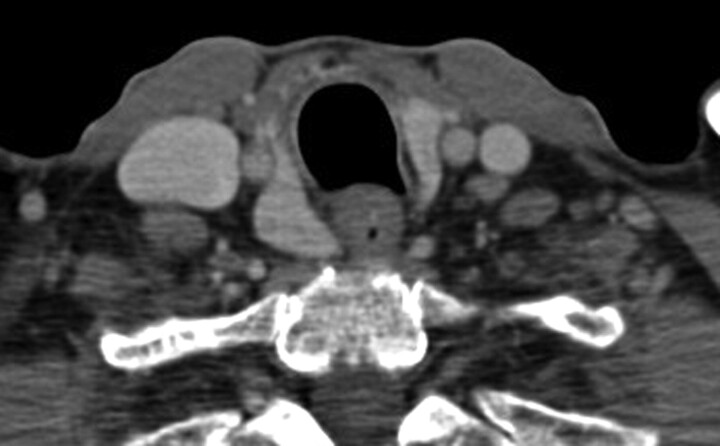

Patient A, our index case, is a 40-year-old woman with recurrent ovarian cancer who presented with symptoms of hoarseness and was found to have a possible metastatic neck lesion. On imaging, the lesion appeared contiguous with the posterior aspect of the right thyroid lobe. On 1 neck CT, it had artifactually lowered attenuation due to streak artifact from the shoulders, but on another CT, it had similar attenuation and enhancement (Fig 4). The right common carotid artery was situated on the lateral aspect of the thyroid and the questionable metastatic lesion. The appearance was stable compared with a remote pulmonary embolism chest CT from 2006 (Fig 6), but due to the initial radiologic concern, a sonography-guided fine-needle aspiration of the nodular area was performed, with pathology read as indeterminate.

Fig 4.

Patient A, with known ovarian carcinoma recurrence in the abdomen, presented with a few weeks' history of voice hoarseness and was noted to have a nodular area posterior to the right thyroid lobe. There was clinical concern for a metastasis or exophytic thyroid nodule.

Patient A's pulmonary embolism chest CT from 2006 shows similar appearance of the questionable thyroid lesion.

Due to ongoing clinical concern by the referring head and neck surgeon, a percutaneous core needle biopsy was performed at our institution (Fig 5), yielding normal thyroid tissue.